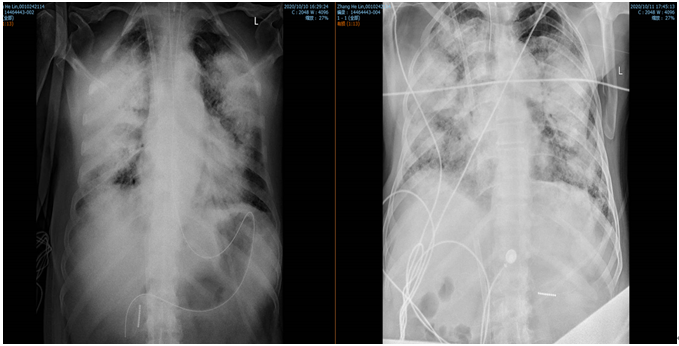

10月14日气道内活动性出血量减少,膜前管路接头处血栓,针对MAP的治疗继续予以甲强龙500 mg冲击,丙种球蛋白20 g/d联合3000 ml血浆置换治疗,患者肺顺应性改善,影像学提示双肺渗出性病变密度较前减轻(图3)

图3  胸部X线片(2020年10月10-11日)

注:双肺渗出性病变持续进展。